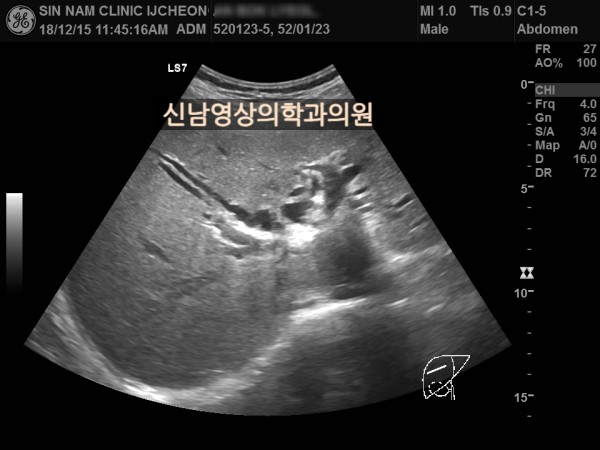

상복부 초음파 적용 사례

본 환자분은 50대 중반의 남성분으로 손가락안이 가렵다는 느낌으로 내원하셨습니다.

담도암과 담관암은 같은 질환을 지칭하는 용어로 간에서 만들어진 담즙이 십이지장으로 이동하는 통로인 담관에 발생하는 악성 종양입니다.

이 암은 간 안에 생기는 간내 담관암과 간 바깥에 생기는 간외 담관암으로 나뉘며, 가장 흔한 증상으로 통증이 없는 황달, 짙은 소변, 옅은 변, 복통, 체중 감소, 소양증 등이 나타날 수 있습니다.

치료는 암의 위치와 진행 정도에 따라 수술, 항암 치료, 담관 스텐트 삽입 등으로 이루어집니다.

담관암의 정확한 원인은 아직 밝혀지지 않았지만 담관 내 만성 염증, 담관 결석, 경화성 담관염, 간디스토마(간흡충증), 염증성 대장 질환 등이 관련 있는 것으로 알려져 있습니다.